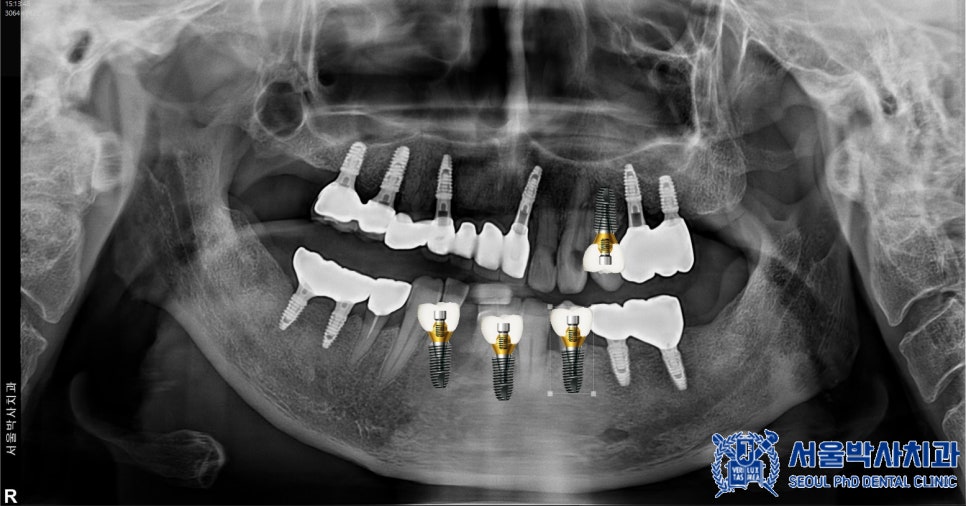

신흥동치과 서울박사에서는

무절개 임플란트

방식을 적용하고 있습니다.

이는 컴퓨터 분석을 통해 미리 계산된 경로를

기반으로 임플란트를 식립하는 방식으로,

수술가이드를 활용하여 절개 없이도

정밀한 수술이 가능한데요.

임플란트 성공률에서 중요한 요소 중

하나는 식립각도로,

식립각도가 임플란트 성패에 얼마나 영향을

서울박사치과에서는 컴퓨터 시뮬레이션을 통해

최적의 식립 위치와 각도를 미리 계산하여

수술을 진행합니다.

약 2개월 후, 임플란트가 안정적으로

자리 잡은 것을 확인한 뒤

최종 보철물을 제작하였습니다.